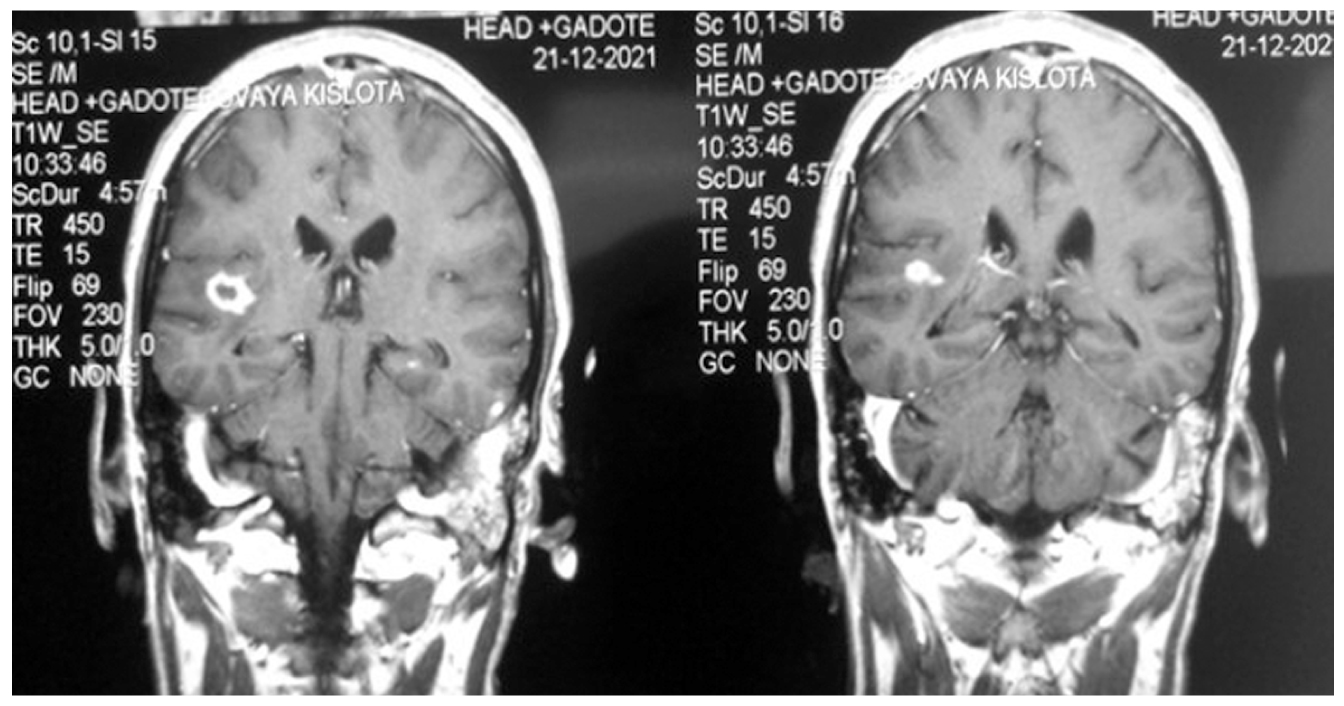

МРТ головного мозга от 21.12.2021 (рис. 2): контрастирование оболочек полушарий мозга (бактериальный менингит), структурные контрастпозитивные изменения в правой височной доле и базальных ядрах, что может соответствовать менингоэнцефалиту с косвенными признаками формирующегося абсцесса.

Рис. 2. Магнитно-резонансная томография головного мозга пациента С. после проведённого лечения.

Консультирован нейрохирургом: «Острый вторичный листериозный менингоэнцефалит с формированием энцефалитического очага в правой височной доле». Показаний к нейрохирургической операции нет.